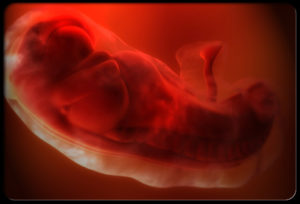

Беременность – это не только миг томительного, но многообещающего ожидания появления на свет самого главного человечка, но серьезное испытание для организма. В этот период внутри женщины происходит серьезная гормональная и физическая перестройка.

Поэтому очень часто на этапе беременности будущая мамочка испытывает некоторые неприятные ощущения. Одним из таких неудобств является странное покалывание в животе. Этот симптом рано или поздно появляется у каждой беременной женщины, и обычно он не ведет за собой ни каких проблем.